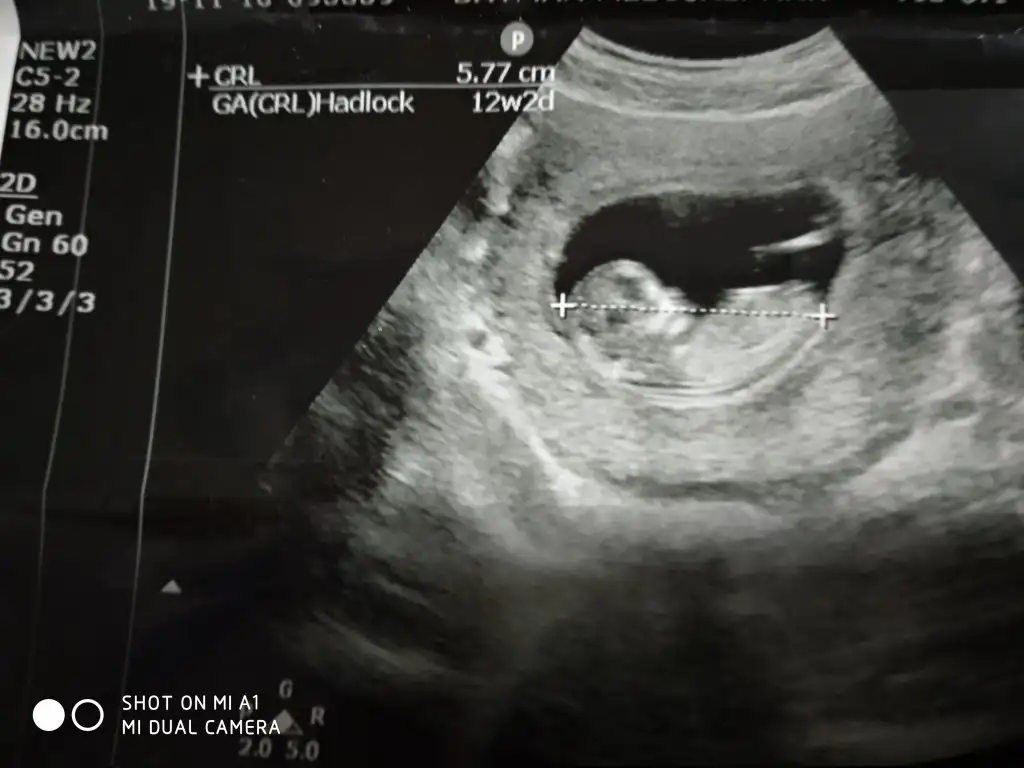

dr soylemeden siz gorun genital nub teorisi ( bebegin cinsiyeti)

Kızlar yorum istiyorum doktor daha küçük dedi 12 haftada ☺️☺️